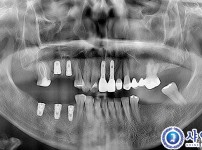

311

상악동거상술 임플란트 12개 - UV자외선